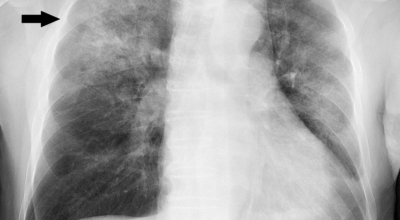

우리나라는 사망률 중 4위가 폐렴일 정도로 폐관련 질환은 위험도가 높다고 합니다. 우리의 몸 면역을 조절해주는 컨트롤 타워가 폐이기 때문에 그만큼 중요하며 호흡기 계통의 질병이 대부분 폐와 관련이 있기 때문에 폐 건강을 항상 챙겨두는 것이 좋습니다. 호흡기 건강, 폐 건강에 있어서는 비타민과 미네랄 그리고 항산화제가 풍부한 음식 몇 가지만 추가해도 체내의 염증을 줄이고 폐 기능을 개선하며 호흡기 건강을 증진시키는데 도움이 될 수 있습니다. 그럼 폐에 좋은 음식 10 가지를 알아보겠습니다.